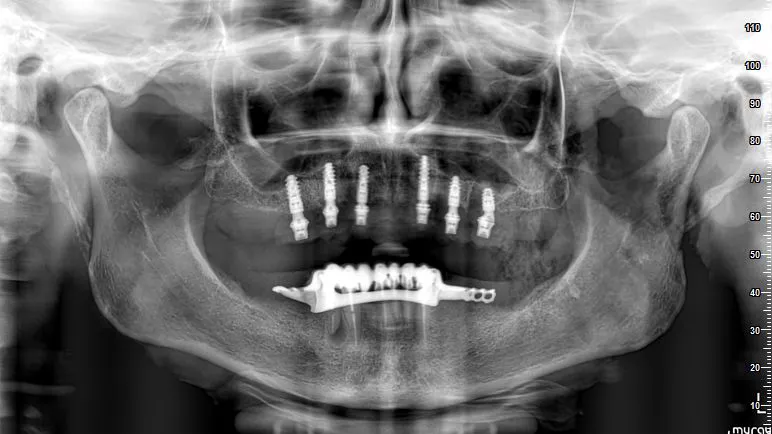

Immediate full-arch rehabilitation with Straumann® Pro Arch BLX (courtesy of J. Caramês)

• Immediate full-arch rehabilitation in the soft bone using Straumann® BLX 3,75 mm from 6 mm till 12 mm in one case (courtesy of B. Sobczak).

• Immediate full-arch rehabilitation using Straumann® BLX 3.75 mm implant in the soft bone (courtesy of L. Cuadrado).

• Immediate full-arch rehabilitation using Straumann® BLX 3.75 mm implant with 10 mm length in the hard bone (courtesy of Dr. L. Swart and P. van Zyl).